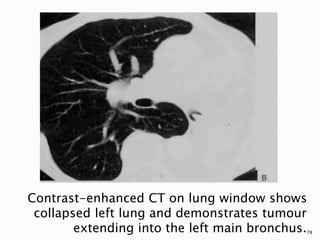

Contrast-enhanced CT on lung window shows

collapsed left lung and demonstrates tumour

extending into the left main bronchus.78

 The level and degree of obstruction by central

tumours leading to atelectasis and

postobstructive pneumonitis can be

visualized easily with cross-sectional

imaging.